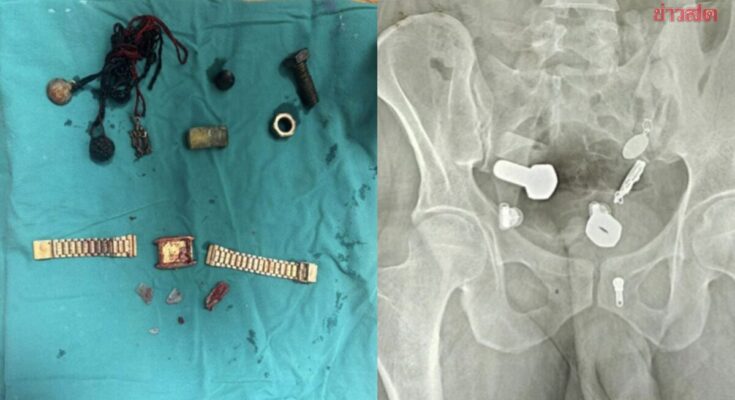

แพทย์ที่ทำการตรวจพบความผิดปกติจากผลเอกซเรย์ ซึ่งแสดงให้เห็นว่า มีนาฬิกาข้อมือติดอยู่ในหลอดอาหาร ขณะที่ในลำไส้ใหญ่พบเศษเหล็กและชิ้นส่วนโลหะต่าง ๆ เช่น น็อต สลักเกลียว และสกรู อัดแน่นสะสมอยู่เต็มไปหมด

แพทย์พยายามใช้วิธีส่องกล้อง (Endoscopy) เพื่อนำวัตถุออก แต่ไม่สามารถทำได้ จึงต้องทำการผ่าตัดใหญ่ที่ใช้เวลานานกว่า 3 ชั่วโมงเพื่อเอาวัตถุทั้งหมดออกจากร่างกาย

รายงานระบุว่า ทีมแพทย์ได้เปิดแผลขนาดเล็กที่ช่องท้องของผู้ป่วย ก่อนค่อย ๆ ดึงวัตถุต่าง ๆ ออกมา ซึ่งรวมถึงนาฬิกาข้อมือเรือนหนึ่ง โดยมีการบันทึกวิดีโอช่วงเวลาที่ศัลยแพทย์นำวัตถุออกมาได้ โชคดีที่หลังจากการผ่าตัดผ่านไป เขาอยู่ในอาการปลอดภัยและกำลังฟื้นตัวได้ดี แม้เหตุการณ์ครั้งนี้จะสร้างความตกตะลึงให้แก่ทีมแพทย์เป็นอย่างมาก